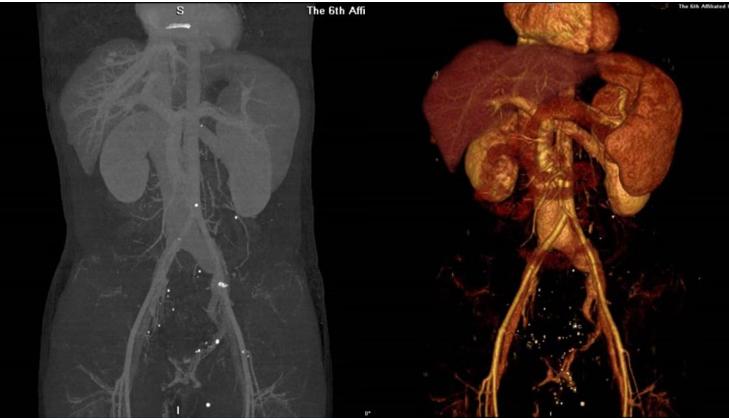

阿超的情况果然符合康亮的猜想。全腹部CT+静脉血管重建成像检查显示盆腔、会阴及臀部皮下多发迂曲静脉;门腔静脉远端属支扩张。诊断意见考虑K-T综合征。

术前CTV及3D重建结果(图示腹盆腔多发畸形静脉)